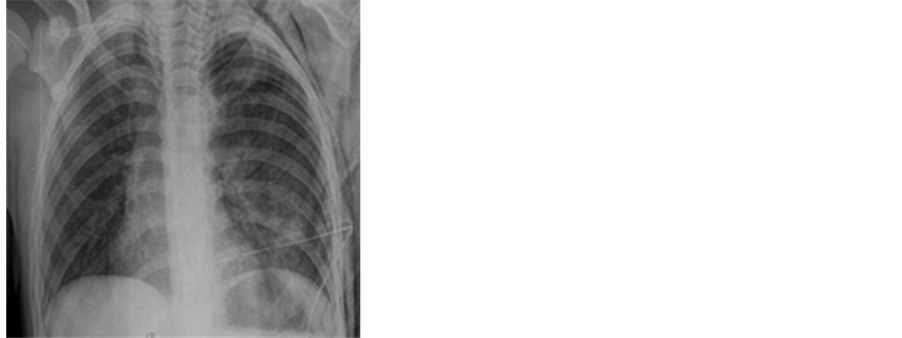

Figure 3. PAAC view following chest tube insertion .

The chest X-ray showed complete ventilation (Figure 3). The tube was re-placed and fixed with dressing. Complete blood count and biochemistry test results were normal. Arterial blood gas values were as follows: pH: 7.39, pO2: 60 mmHg, and pCO2: 39 mmHg. Abdominal ultrasonography findings showed no abdominal trauma. The patient was hospitalized with stable signs in the Department of Chest Surgery Clinic. The patient was not operated on, as the arterial blood gas value and other laboratory values were within normal ranges and respiratory movements of the chest wall returned to normal. He was discharged on the sixth postoperative day. Repeated examination and radiographs on the 15th day after discharge showed normal results.